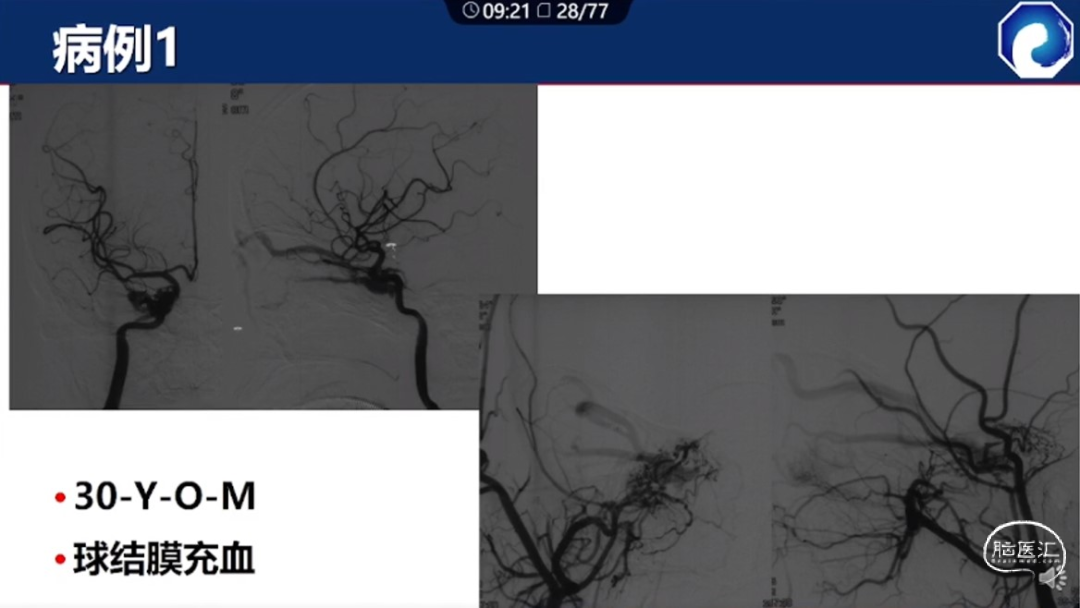

痿口静脉端的识别至关重要。

痿口静脉端精准完全闭塞是DAVF治愈的关键。

靶向性栓塞可以减少海绵窦分隔的过渡栓塞,有利于减少颅神经并发症,恢复海绵窦的正常引流功能。